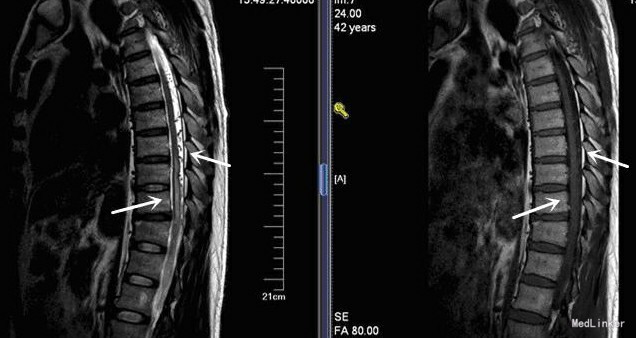

查体:神清语明,步态平稳,查体合作,双瞳孔等大正圆,D=3.0mm,对光反射灵敏,双眼球各向运动充分,无眼震,无复视,额纹对称,双侧鼻唇沟对称,示齿口角不偏,伸舌居中,咽反射存在,转颈耸肩对称有力,双上肢肌力Ⅴ级,双下肢肌力Ⅴ-级,肌张力正常,双下肢痛觉减退,左侧较重,深感觉未见异常,双侧指鼻、轮替、跟膝胫试验稳准,闭目难立征及走直线征阴性,BCR L++R++,PSR L+++R+++,Babinski征L-R-,颈软。余神经系统查体未见明显异常。 胸段增强MRI检查:胸9椎体上缘水平以下脊髓普遍增粗肿胀,其内见模糊长T1、长T2信号斑片,增强扫描局部似见少量点状轻度强化,脊髓后蛛网膜下腔内多发血管流空信号影

脊髓硬脊膜动静脉瘘 将患者转入上一级医院手术治疗。